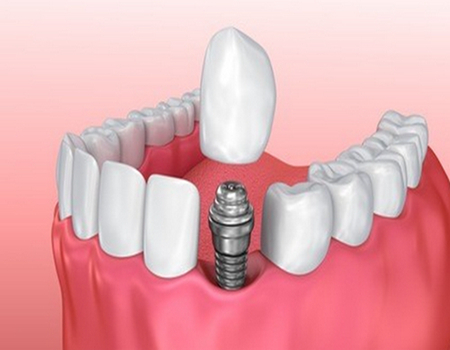

何斌:自从在重庆医科大学毕业之后,就参加了口腔临床工作,有着20多年的工作经历,针对各种口腔疾病的诊疗技术都是很擅长的,并且掌握到了更丰富的临床经验,尤其比较擅长各种牙体牙髓疾病的诊疗,以及各种复杂牙齿疾病的诊治,得到了很多牙友们的信任和支持。手术之前还能够利用x光机对患者的牙齿情况进行检查,了解到牙齿的情况之后,才能够进行手术方案的定制,得到了很多患者们的信任与支持。

何斌医生可以说技术是很不错的,尤其是在做各种牙体牙髓疾病的诊疗方面造诣很深。医生从事口腔临床工作多年,掌握到了更多的知识,并且经常参加学术交流会议,拥有自己独特的手术技巧和手术方案,获得了很大的名气以及荣誉称号。在做牙髓疾病以及根尖周病诊疗的时候,手法操作很娴熟,尤其比较注重细节的问题,可以减轻手术过程当中的疼痛,而且做完牙齿诊疗之后,能够让牙齿恢复到健康的状态,相对也是比较稳固的。

重庆口腔医院牙体牙髓科是属于该医院的特色专科,并且这里的医护人员都是很专业的,在做各种牙体牙髓疾病诊疗的时候也都很有经验。可以了解到患者们的整体需求,并且引进了进口的医疗设备,进行各种口腔疾病诊疗的时候,都能够进行详细的检查。该科室还完成了不少的口腔疾病诊疗案例,比较注重消毒管理,在做手术之前也能够进行各方面的消毒检测,能够让患者们在比较安心的环境下做口腔疾病的诊疗。

作为重庆医科大学附属口腔医院的主治医师,该医生在各种牙体牙髓疾病以及龋齿疾病诊疗等多个方面都颇有研究,有着自己独特的手术操作技巧。手术之前会认真检查每一位患者的口腔情况,了解他们的诉求,然后制定适合的手术方案。整个手术操作手法是相当娴熟的,能够尽可能的减少手术创伤,而且术后还会提供相应的恢复方案,致力于让每一位患者在这里能够得到比较好的就诊体验。